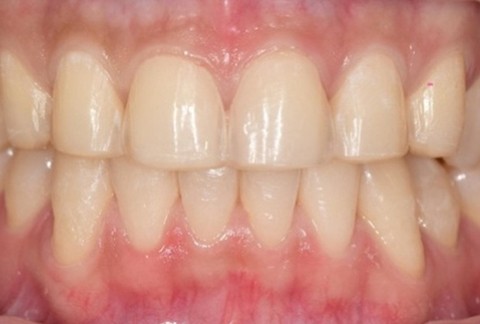

임플란트-전후사진